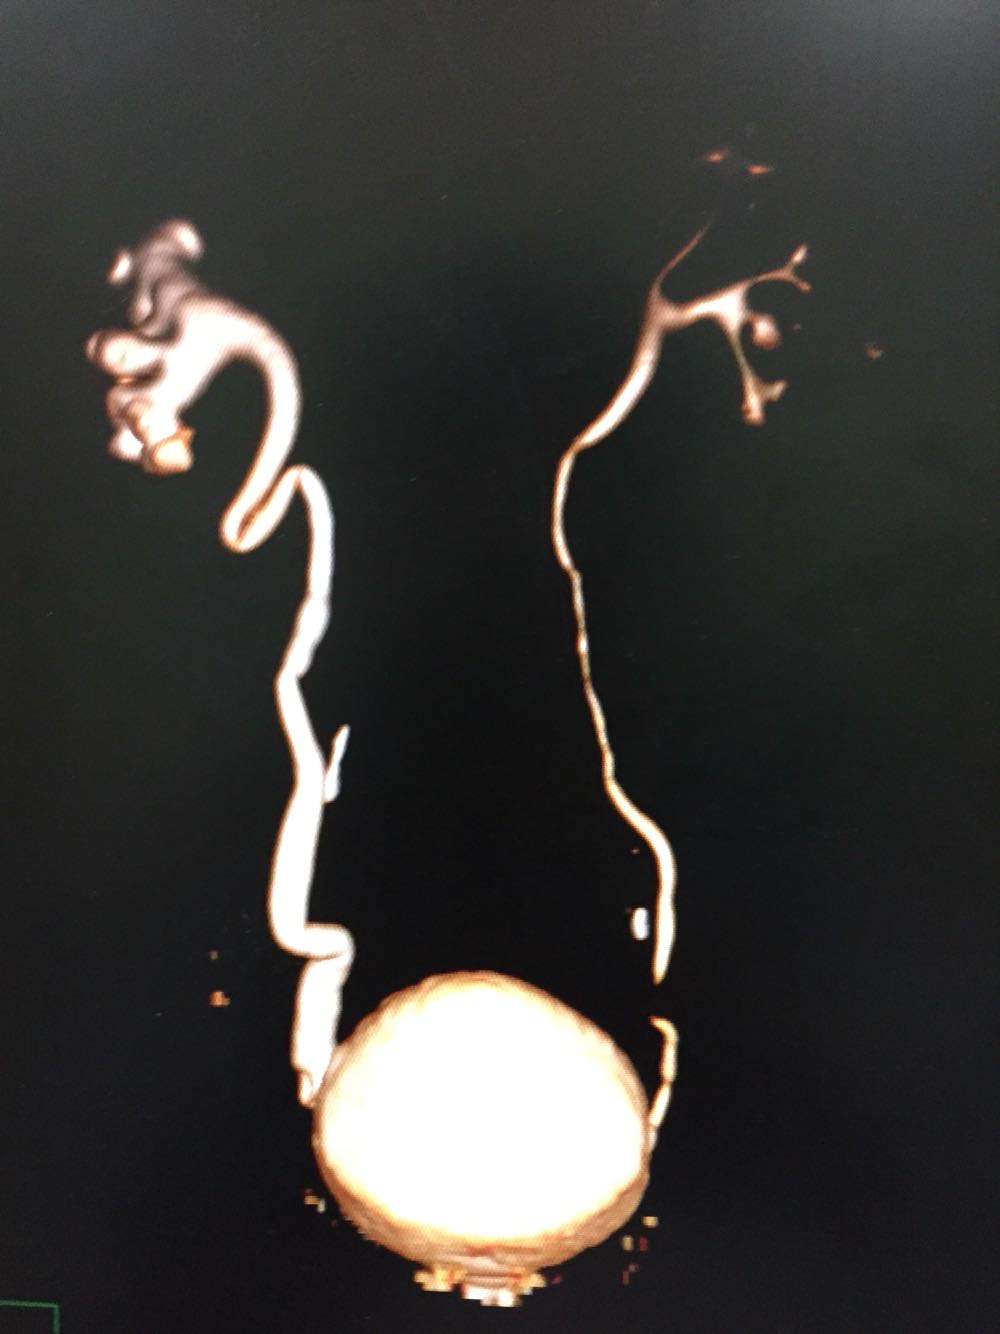

右肾区叩痛阳性。 CTU提示右侧输尿管下段肿瘤,右肾积水。 尿脱落细胞提示,查见癌细胞。

右侧输尿管下段癌,行后腹腔镜下右侧输尿管癌根治性切除术